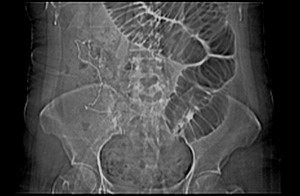

女 42岁 子宫肌瘤于外院术后两天,感腹胀。x线提示肠梗阻。

子宫肌瘤于外院术后两天,出现肠扭转梗阻,很明显。但右下腹部出现的线状高密度,是什么呢?有什么手术会有这样的物品呢?不会把电刀的导线遗留在腹腔吧!?

结果:术后纱布遗留,术后麻痹性肠梗阻肠梗阻

上面的图像是我们从手术室拿来的纱布做了个ct平扫,发现纱布里确实存在有一条致密影。后得知致密影是为防止手术时纱布遗留而设计。关腹时怀疑纱布遗留可做个床边透视或拍片可明确。